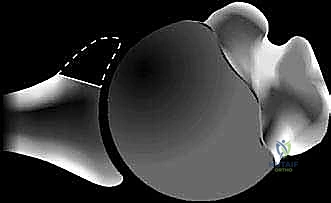

في الحالة الطبيعية، يكون الجزء السفلي من التجويف الحقاني أوسع من الجزء العلوي (شكل الكمثرى الطبيعي). ولكن مع تآكل العظم الأمامي السفلي، يفقد التجويف الحقاني عرضه في هذه المنطقة الحرجة. النتيجة هي أن الجزء العلوي يصبح أوسع من الجزء السفلي، مما يخلق شكل "الكمثرى المقلوبة".

الشكل 2 • يؤدي فقدان العظم الأمامي للتجويف الحقاني (الخط المتقطع في الصورة الأولى) بسبب التآكل أو الكسر إلى فقدان عرض التجويف الحقاني (A) وعمقه (B). والنتيجة هي شكل كمثرى مقلوبة لا يمكنه مقاومة إزاحة رأس العضد الأمامية بفعالية مثل التجويف الحقاني الطبيعي على شكل كمثرى.

عندما يصل المريض إلى هذه المرحلة، فإن الآلية الطبيعية لـ "ضغط التقعر" تنهار تماماً. يصبح المفصل غير قادر على احتواء رأس العضد، ويحدث الخلع لأتفه الأسباب، مثل العطس، أو التقليب في السرير أثناء النوم، أو مجرد رفع الذراع لارتداء الملابس.